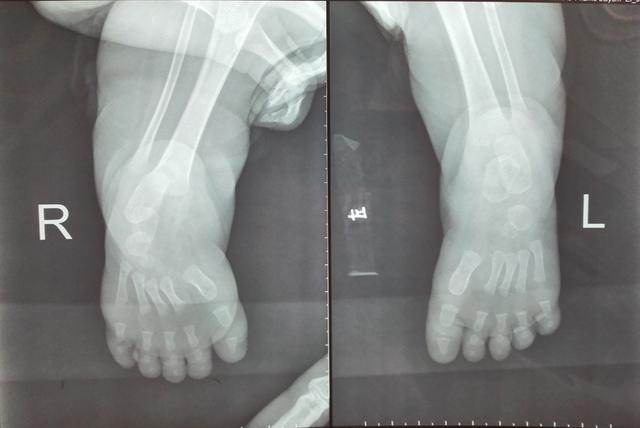

快停止:幼兒使用學步車,腿腳變畸形

2歲的菲菲家住漢口,出生后媽媽發(fā)現(xiàn),女兒的大動作總是比同齡孩子慢半拍,4個月還不會翻身,7個月還不能坐。擔心將來走路晚,媽媽決定買來學步車讓她提前練走。1歲3個月時,菲菲可以完全丟手走了,媽媽很是高興。過了一段時間,媽媽又發(fā)現(xiàn)不對勁了:女兒走路老喜歡踮著腳尖,步態(tài)像只“鴨子”,到醫(yī)院拍片檢查顯示:左側(cè)跟骨發(fā)育不良,雙足內(nèi)翻,診斷為馬蹄內(nèi)翻畸形。醫(yī)生給菲菲做了矯型手術,還要再做一段時間的康復治療。

媽媽帶著她在武漢市第一醫(yī)院康復科做了2個月的康復訓練后,菲菲的步態(tài)明顯改善,但要想完全恢復正常,還要至少再佩帶半年的支具。

市一醫(yī)院康復科醫(yī)師高李俠說,小孩的骨骼和成年人不一樣,他們需要在學習坐、爬、走的過程中,逐漸獲得與行走相匹配的適應能力。行走是負重運動,當關節(jié)肌肉還未達到負重的要求時,過早起步會影響孩子下肢的發(fā)育,導致“X”或“O”形腿。他提醒,7個月的寶寶坐學步車,腳不能完全著地,只能用腳尖觸地滑行,時間一長就形成前腳掌觸地的踮腳走路姿勢,逐漸形成馬蹄內(nèi)翻畸形,而且學步車過輕,嬰幼兒在快速移動過程中摔傷者也屢見不鮮。